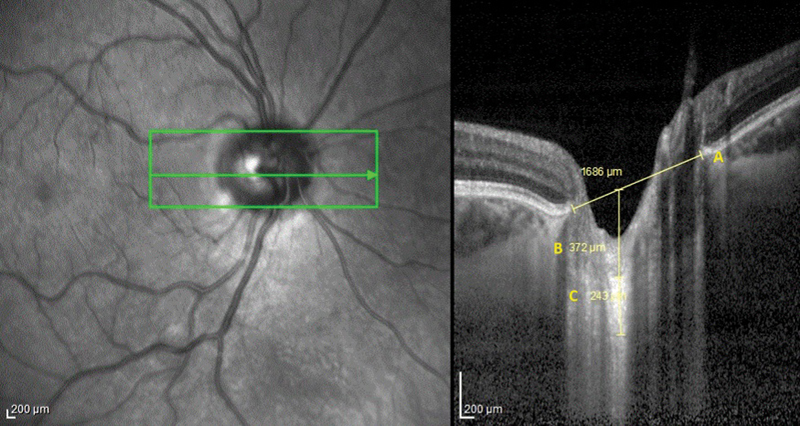

Methods:  The sample in the present study consisted of 20 recently diagnosed MCI patients, 20 recently diagnosed AD patients, and 20 matched healthy volunteers. Every patient underwent magnetic resonance imaging (MRI) scans. The VolBrain software (open-access platform for MRI brain analysis) was used to calculate the hippocampal volume. Optical coherence tomography was performed to measure the LCT. Analysis of variance and Pearson chi-squared tests were employed to assess the results.

Results:  The lowest total hippocampal volume (p < 0.05) was in the AD group, which was 6.14 ± 0.66 mm3, while in the control group, it was 7.7 ± 9.65 mm3, and 6.69 ± 0.46 mm3 in the MCI group. In comparison to the rest of the groups, in the AD group, the LCT was the thinnest (202.17 ± 16.35 µm). As per the results of the study population as a whole, low hippocampal volume causes low LCT, which shows an important relationship (r: 0.41; p < 0.05).